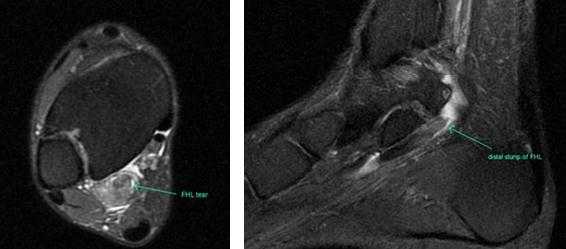

Прежде всего, это боль по задне-внутренней поверхности голеностопного сустава. Возможно «защёлкивание» большого пальца при его сгибании. Хруст, крепитация по задне-внутренней поверхности голеностопного сустава при активных движениях. При физикальном осмотре определяется боль при сгибании большого пальца через сопротивление, при форсированном подошвенном сгибании в голеностопном суставе, при этом боль отсутствует в области первого плюсне-фалангового сустава. Для диагностики повреждения сухожилия длинного сгибателя большого пальца стопы целесообразно выполнение МРТ, при этом обнаруживается скопление жидкости вокруг сухожилия на уровне голеностопного сустава, изменение сигнала от самого сухожилия.

Повреждения сухожилия сгибателя большого пальца стопы распространённый вид травмы в таких группах риска как танцоры (прежде всего балета), гимнасты и скалолазы. Эти группы людей объединяет существенная перегрузка сгибателя большого пальца стопы при выполнении толчков и зацепов, стояния на пуантах. Вторым названием данной патологии является «тендинит танцора». В остальной популяции данные повреждения встречаются крайне редко. Так как сухожилие длинного сгибателя большого пальца проходит в фиброзно-костном канале позади внутренней лодыжки и голеностопного сустава, оно оказывается как бы перекинутым через задний отросток таранной кости, как верёвка перекинутая через блок.

При его хронической травматизации дегенеративные изменения приводят к его утолщению и уплотнению, вызывают его сдавление и ущемление. Может возникнуть так называемый задний импиджмент голеностопного сустава. В случае если в толще сухожилия возникают узелки, может появиться такой симптом как «триггерный палец», когда большой палец согнувшись «защёлкивается», и разогнуть его можно только через боль и приложив значительное усилие. При длительно текущем процессе возможно рубцовое сращение сухожилия со своим каналом, что приводит к псевдо-ригидной деформации первого плюсне-фалангового сустава.

При разрывах сухожилия длинного сгибателя большого пальца помимо остро возникшей боли и отёка по задне-внутренней поверхности голеностопного сустава определяется выраженная слабость подошвенного сгибания большого пальца стопы.